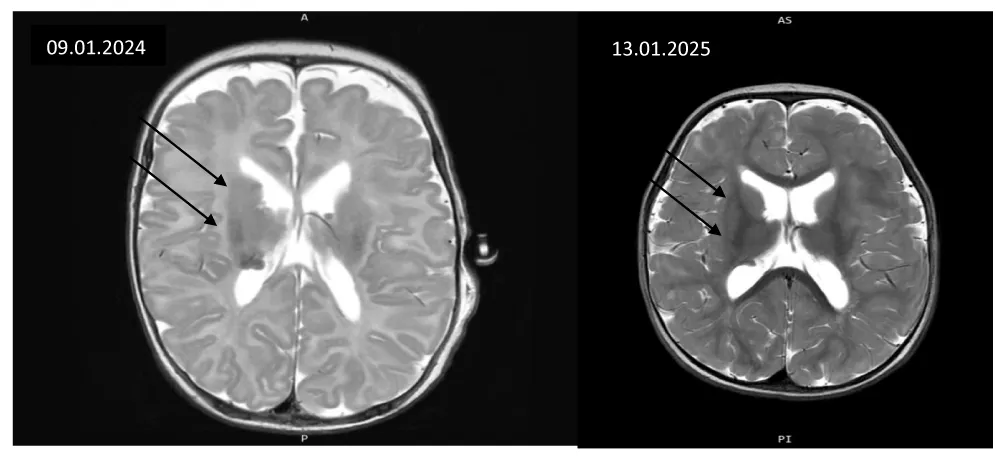

MRI-confirmed SEGA diagnosis pre-therapy and at 12 months showed partial response without significant size progression (Figure 4).

Main CNS lesions were subependymal along both lateral ventricles, with normal ventricular morphology. MRI follow-up showed no lesion progression and slight tumor shrinkage.